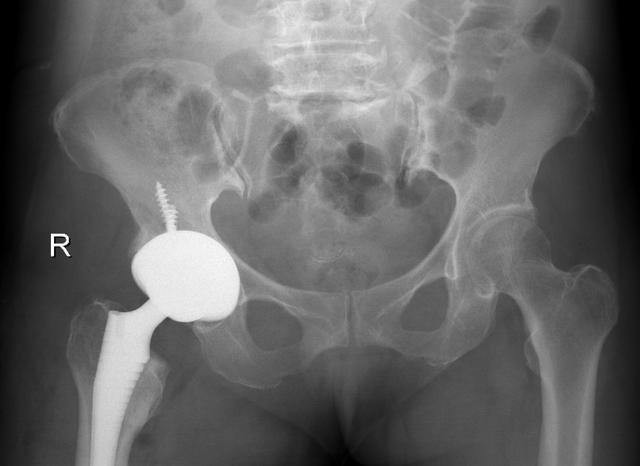

▲术后影像资料

根据患者的情况,科室手术团队在李宝军主任带领下,经过术前精心设计、测量,成功为朱女士实施了全髋关节置换手术。术后第一天朱女士即能下地行走,髋部走路疼痛感消失,双下肢长度恢复等长,步态也恢复正常。患者及家属对手术效果非常满意。